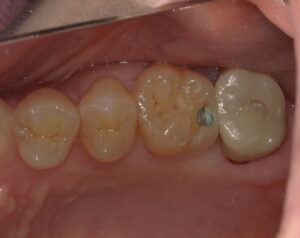

詰め物を外してから青い液で染め出したらけっこう中で広がっていました。

虫歯を全て除去しました。神経近くまで広がっていました。

ダイレクトボンディングで修復しました。